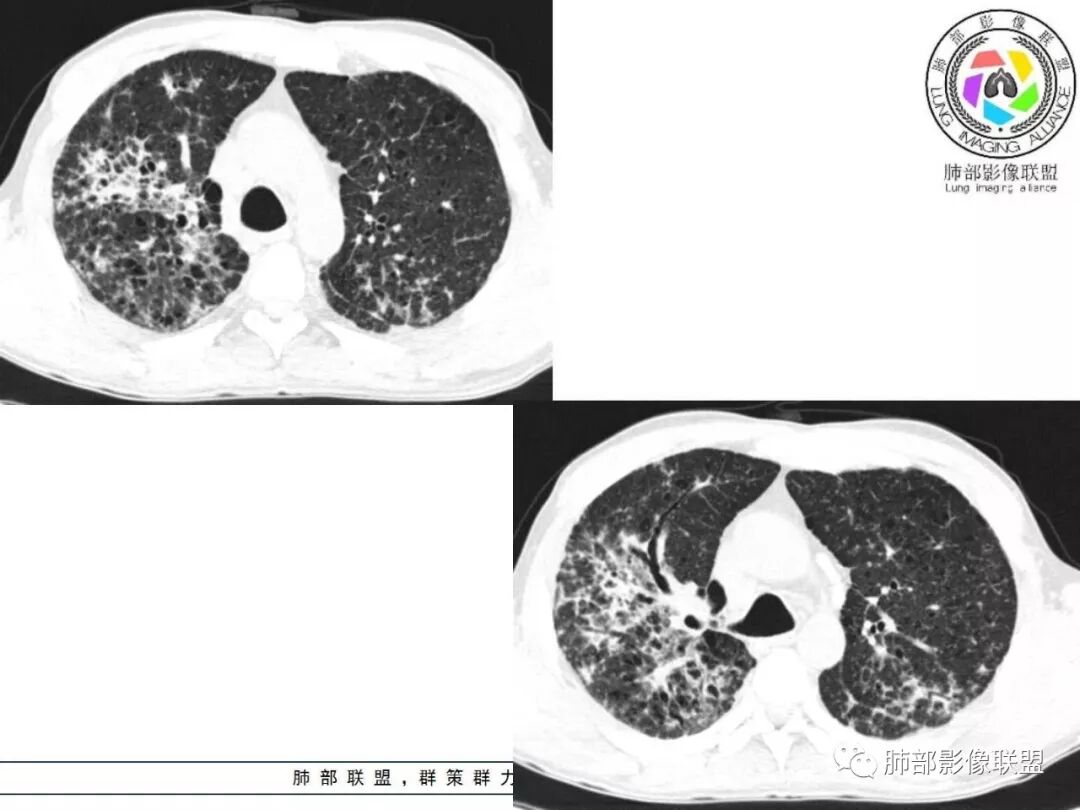

胸部CT:两肺弥漫病灶,磨玻璃影,少许实变,部分累及胸膜,磨玻璃区可见囊?少许胸腔积液,两肺可见结节,支气管血管束增粗,小叶间隔增厚,支气管走形有扭曲扩张,可见纤维化。气肿、大泡。考虑:感染性病变,PCP?查下HIV,CD4,G等。鉴别结核、结缔组织病肺浸润。

患者中年男性,发热1月,体温38℃-39℃,峰值40℃,无畏寒、寒战,伴黄痰,CRP升高明显,降钙素原稍升高,血沉、血糖正常。胸部CT:两肺弥漫病变,磨玻璃影+点片渗出,部分累及胸膜,磨玻璃区边界清楚,少许胸腔积液,两肺支气管血管束增粗,小叶间隔增厚,部分支气管走形有扭曲扩张,可见肺气肿、右肺尖肺大泡及部分纤维化改变。综合考虑:感染性病变。结核或PCP可能性大,鉴别风湿免疫、结缔组织疾病肺浸润和腺癌等恶性病变。

双肺弥漫性病变,多发磨玻璃密度及小叶间隔增厚,大部分沿支气管血管束分布,伴支气管轻度扩张,以午后及晚上发热为主,考虑感染性病变,间质性结核可能大,另双肺多发肺气囊,LIP待排

双肺病灶,以间质性病灶为主,支气管壁增厚,可见树芽征改变,考虑感染性病变,间质性结核可能。

两肺弥漫性病变,沿支气管血管束分布,部分细支气管轻度扩张,两上中肺为主,部分累及胸膜下,部分磨玻璃影,部分纤维化,肺气肿肺大疱背景,胸膜增厚,少量积液,病程一月余,crp高反复发热,两肺门区增大钙化淋巴结,间质性疾病,考虑淋巴增殖性病变为主,结核可能性大,待鉴别NTM,结节病,LIP,PCP纤维化

两肺弥漫性病变,沿支气管血管束分布,部分细支气管轻度扩张,两上中肺为主,部分累及胸膜下,部分磨玻璃影,部分纤维化,肺气肿肺大疱背景,胸膜增厚,少量积液,考虑结核可能性大,鉴别op、LIP,PCP纤维化

中老年男性,发热1月余,双肺弥漫性病变,多发网格、结节、斑片状实变影及磨玻璃影,胸膜下及中轴间质都受累,支气管血管束增粗、变形,支气管扩张,叶间裂及小叶间隔增厚,整体间质性改变明显,考虑结核?OP、LIP?进一步除外PCP、肿瘤、结节病等。

病变一般沿血管支气管束分布或小叶分布,一般上肺多于下肺(这与常见继发性肺结核分布相若)。

常会伴有其他继发性肺结核病灶,如斑片影、结节影,树芽征,新旧不等改变。

2. 肺气肿背景(小叶中心性肺气肿);双肺多发病灶整体沿血管支气管束及胸膜下分布,以上叶及下叶背段分布为主,有实变及GGO,边界清楚,有树芽,小叶间隔及中央间质增厚,叶间裂见到多发结节,部分支气管不规则牵拉扩张,提示病灶纤维化明显,结合临床病史,考虑病灶为间质性感染,肺门及纵隔内有钙化淋巴结,小叶间隔结节,考虑淋巴道增值性疾病可能,综合常规要怀疑间质性肺结核。